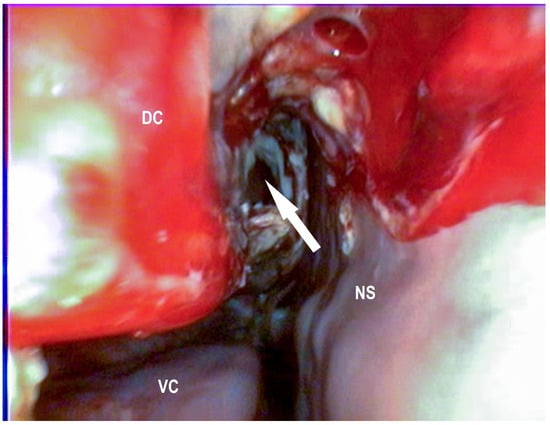

2.2.4. Endoscopic Guided Conchotomy

2.2.5. Transendoscopic Laser Fenestration of the Nasal Conchae